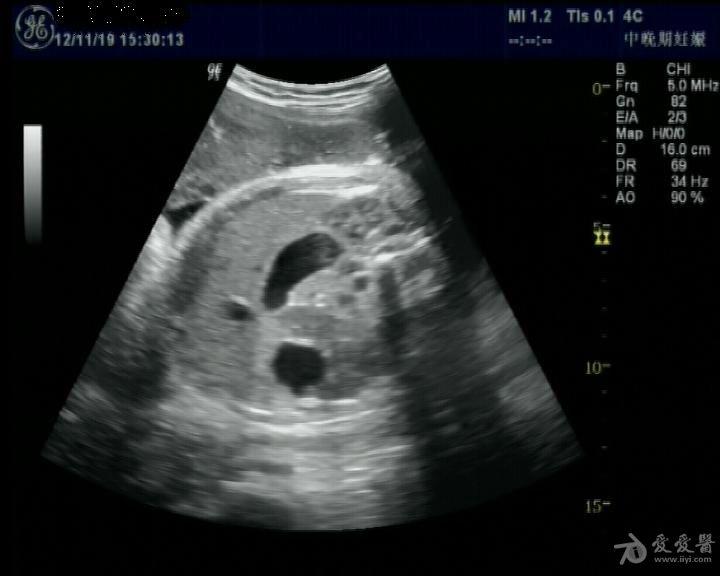

胎儿腹部双泡征

胎儿胃,十二指肠扩张,呈"双泡征".

晚妊 胎儿 双泡征